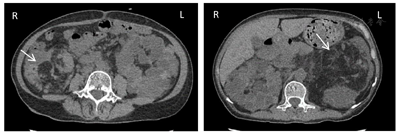

腹部彩超:多囊肾声像图改变;双肾结石;双侧输尿管无扩张;肝内实性病灶;肝多发囊肿;胆胰脾未见明显异常。心电图及心脏彩超未见明显异常。全腹部CT平扫(图1):双肾改变,考虑多囊肾、部分为复杂囊肿,合并多发错构瘤,以左肾为显著;肝内多发低密度灶,囊肿。胸部CT平扫(图2):双肺多发囊腔,考虑肺淋巴管肌瘤。胸椎及肋骨多发结节状高密度灶。头颅MRI平扫(图3):双侧额叶、左侧顶叶、右侧颞叶皮质及皮质下结节状异常信号。

TSC患者中肾错构瘤(即肾血管平滑肌脂肪瘤)的发生并不罕见,约80%病例可合并[4]。TSC合并肾错构瘤多为良性肿瘤,但在儿童及成人中也有合并恶性肿瘤的报道,但发病率低为1%~2%。即使如此也需要进行鉴别诊断,影像学表现不能排除恶性肿瘤时需要进一步行活检明确诊断。并TSC的肾错构瘤具有多发性、双侧性、增长速度快等特点,其肿瘤每年增大约20%,与单纯错构瘤相比肿瘤破裂出血风险性更大,尤其当肿瘤直径>30 mm时[4,5]。

由于TSC1、TSC2基因突变导致TSC合并多囊肾的发病率也明显高于普通人群。2012年国际结节性硬化症共识会议对TSC诊断标准进行了修订[1],将基因检测列为独立的诊断标准,通过基因检测可鉴定出TSC1或TSC2致病突变即可确诊TSC。15%~25%的TSC患者通过常规基因检测未能检出突变,故基因检测阴性不能排除TSC,亦不作为TSC诊断金标准。当临床诊断疑似时可行基因诊断。临床诊断标准包括:主要特征:(1)色素脱失斑(≥3个,直径≥5 mm);(2)面部血管纤维瘤(≥3个)或头部纤维性斑块;(3)甲周纤维瘤(≥2个);(4)鲨革斑;(5)多发性视网膜错构瘤;(6)脑皮质发育不良(包括结节和脑白质辐射状迁移线);(7)室管膜下结节;(8)室管膜下巨细胞星形细胞瘤;(9)心脏横纹肌瘤;(10)肺淋巴管肌瘤病;(11)肾脏血管平滑肌脂肪瘤(肾错构瘤)。次要特征:(1)"斑驳状"皮肤改变;(2)牙釉质点状凹陷(≥3个);(3)口腔内纤维瘤(≥2);(4)视网膜色素缺失斑;(5)多发肾囊肿;(6)非肾脏错构瘤。具有2个主要特征,或1个主要特征加2个次要特征可确诊;具有1个主要特征,或1个主要特征加1个次要特征,或≥2个次要特征为疑似。

TSC可累及多脏器多系统,根据发病年龄受累器官不同,其临床表现也不尽相同。有学者将其主要临床表现归纳为血管纤维瘤、癫痫发作及智力减退三联征。本例患者无上述临床表现,诊断上易出现误诊、漏诊。本例患者TSC诊断得益于腹部、胸部及头颅影像学对各系统检查提示:同时具有多个肾错构瘤、肺淋巴管肌瘤、大脑皮质及皮质下多发结节3个主要特征及多发肾囊肿1个次要特征。患者目前规律随访中,病情无进展。根据2012年TSC专家共识院外仍需定期进行腹部及头颅影像学检查,及对肾小球滤过率及血压进行定期评估。TSC为常染色体显性遗传,疾病根据个体发育阶段的不同而有不同发展。患者儿子患多囊肾,进一步腹部、头部影像学检查有助于排查有无脏器受累。基因检测亦可用于遗传咨询或诊断不明确情况下。